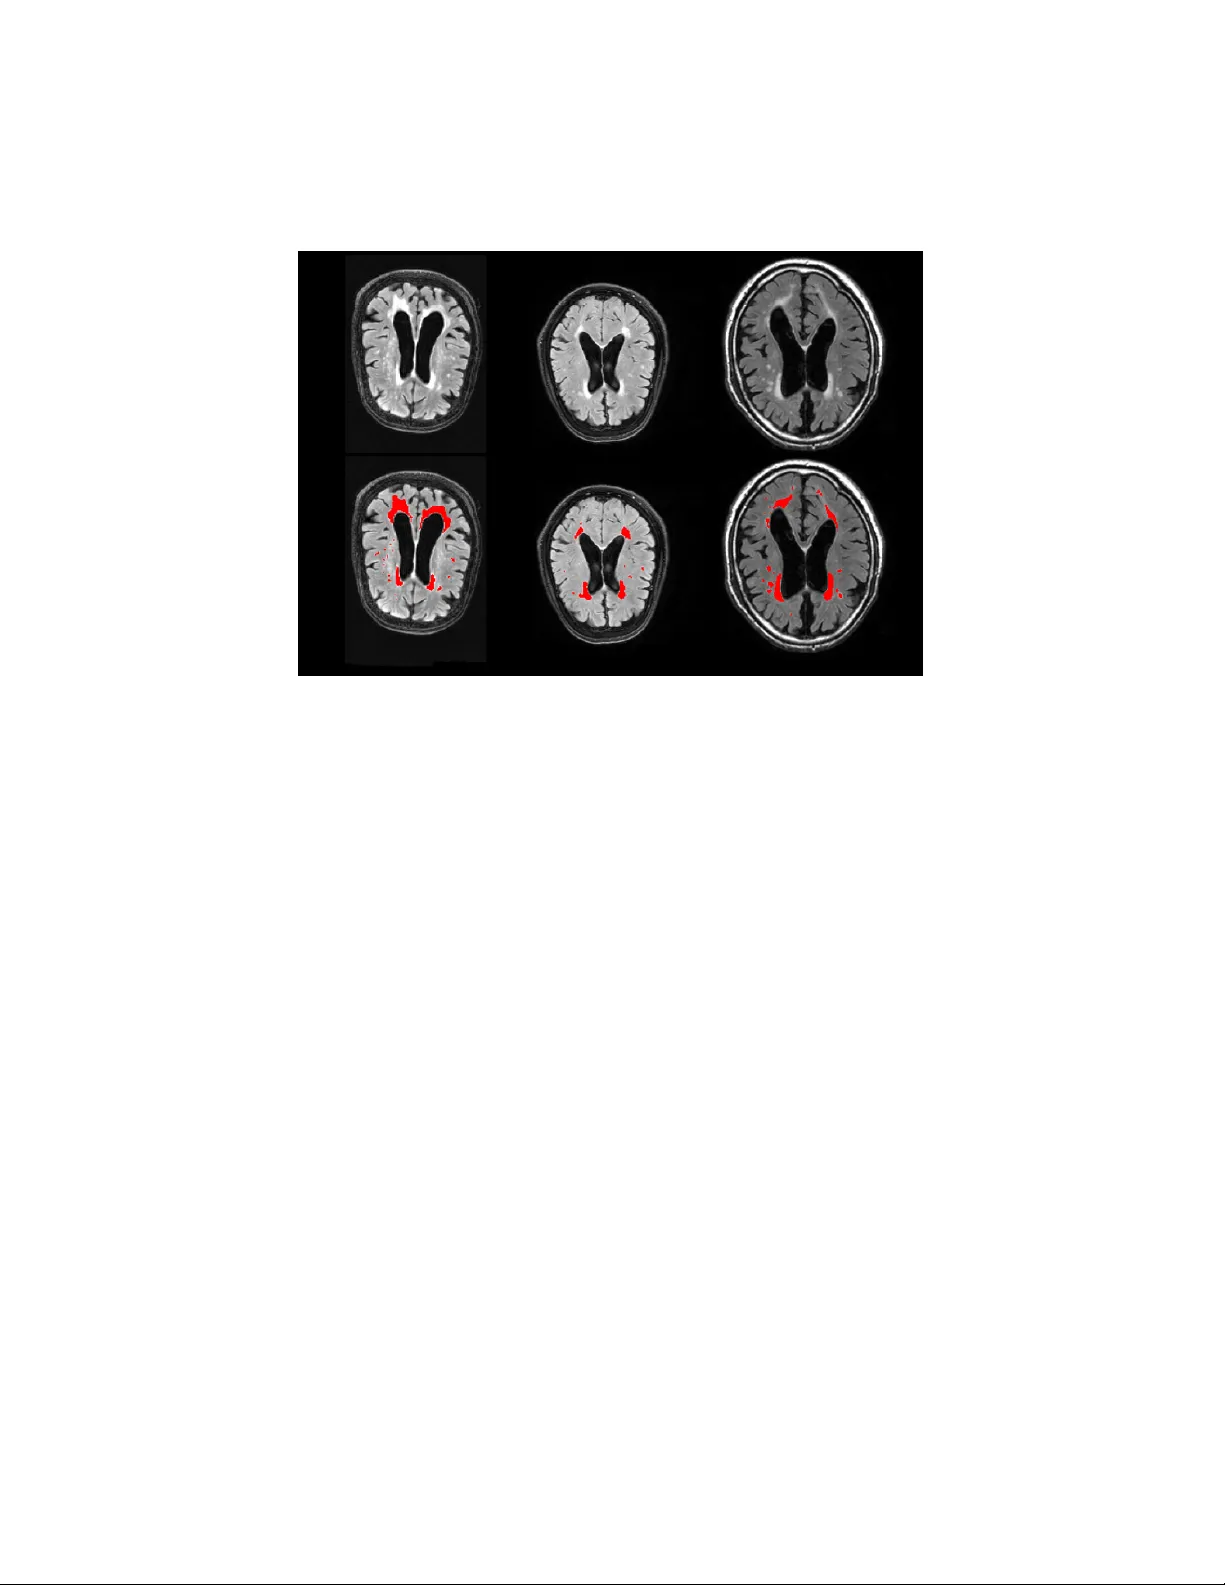

본 논문은 뇌 영상 분석에서 핵심적인 역할을 하는 해부학적 및 병변 분할 작업을 위해 새로운 딥러닝 기반 프레임워크인 DeepMRSeg를 제안한다. 기존의 UNet 구조는 뛰어난 성능을 보였지만, 스케일 다양성 부족, 깊은 네트워크 학습 시 발생하는 그래디언트 소실, 그리고 max‑pool에 의한 경계 손실 등의 한계가 존재한다. 이를 해결하기 위해 저자들은 세 가지 주요 설계 요소를 도입하였다. 첫 번째 설계 요소는 인코더와 디코더 양쪽에 ResNet 잔차 블록을 삽입한 것이다. ResNet은 입력 신호를 그대로 전달하는 shortcut 연결을 통해 네트워크가 잔차 매핑을 학습하도록 하여, 층이 깊어져도 학습이 안정적으로 진행되도록 돕는다. 이는 특히 3D MRI와 같이 데이터 차원이 높은 경우에 유용하며, 모델이 더 깊어질수록 성능이 향상되는 효과를 가져온다. 두 번째 설계 요소는 Inception‑ResNet‑A 구조를 변형한 ResInc 모듈이다. 이 모듈은 입력 피처맵을 네 개의 병렬 브랜치로 분할하고, 각각 1×1, 3×3, 5×5 등 다양한 커널 크기의 컨볼루션을 적용한다. 각 브랜치는 서로 다른 수용 영역을 학습함으로써 다중 스케일 특징을 동시에 추출한다. 이후 1×1 컨볼루션을 통해 차원을 재조정하고, 잔차 연결을 통해 원본 피처와 결합한다. 이러한 구조는 파라미터 수를 크게 늘리지 않으면서도 네트워크 폭을 확대할 수 있게 해준다. 저자들은 ResInc 모듈이 전통적인 ResNet 블록 대비 파라미터 수가 약 1/3에 불과함을 강조한다. 세 번째 설계 요소는 전통적인 max‑pool 대신 stride‑2 1×1 컨볼루션을 사용한 Transition Down 블록이다. 이 블록은 다운샘플링 과정에서 학습 가능한 가중치를 통해 피처맵을 축소하므로, 단순히 최대값을 선택하는 max‑pool에 비해 경계 정보를 더 잘 보존한다. 또한, 이 과정에서 피처맵 수를 두 배로 늘릴 수 있어 디코더 단계에서 풍부한 정보를 활용할 수 있다. Upsampling은 transposed convolution(1×1, stride 2)으로 수행되며, 인코더의 skip connection과 결합해 정확한 위치 정보를 복원한다. 학습 과정에서는 softmax cross‑entropy, 평균 제곱 오차(MSE), 그리고 soft Intersection‑over‑Union(IoU)를 동일 가중치로 합산한 복합 손실 함수를 사용한다. 이는 픽셀‑레벨 정확도와 영역 겹침을 동시에 최적화하도록 설계된 것이다. 최적화 알고리즘은 Adam이며, 초기 학습률 0.05에 매 epoch마다 0.98의 감쇠율을 적용한다. 데이터 증강으로는 좌우 플립, 무작위 회전·이동, 밝기·대비 변화를 적용해 모델의 일반화 능력을 강화하였다. 평가에서는 세 가지 공개 데이터셋을 사용하였다. 첫 번째는 MICCAI 2017 백색질 병변(WML) 챌린지 데이터로, 60명의 피험자에 대해 T1 및 FLAIR 스캔과 전문가가 만든 병변 마스크가 제공된다. 두 번째는 MICCAI 2013 심부 뇌 구조 데이터로, OASIS 프로젝트의 T1 스캔과 14개의 뇌 구조(양측) 라벨이 포함된다. 세 번째는 Medical Decathlon 해마 데이터로, 195명의 피험자에 대한 3D T1 MPRAGE와 해마 몸통·꼬리 라벨이 제공된다. 각 과제마다 4‑fold 교차 검증을 20회 반복해 평균 및 표준편차를 보고하였다. 비교 대상은 배치 정규화 레이어만 추가된 기존 UNet이며, 손실 함수와 데이터 증강은 동일하게 유지하였다. 실험 결과, DeepMRSeg는 평균 Dice(또는 F1) 점수에서 기존 UNet 대비 2~5% 향상을 보였으며, 특히 작은 병변이나 복잡한 경계가 있는 구조에서 F2 점수와 Balanced Accuracy가 현저히 개선되었다. 파라미터 효율성 측면에서도 ResInc 모듈 덕분에 전체 파라미터 수는 기존 ResNet 기반 UNet 대비 약 30% 수준으로 감소하면서도 네트워크 깊이와 폭을 확대할 수 있었다. 마지막으로 저자들은 코드와 사전 학습된 모델을 온라인 플랫폼(IPP)에서 공개함으로써, 연구자와 임상가가 별도의 환경 설정 없이 바로 적용할 수 있도록 하였다. 이는 재현성을 높이고, 다양한 연구 분야에서 빠른 프로토타이핑과 임상 적용을 촉진한다는 점에서 큰 의미를 가진다. 요약하면, DeepMRSeg는 다중 스케일 특징 추출, 잔차 학습, 경계 보존이라는 세 가지 혁신적 설계를 결합해 MRI 기반 뇌 구조 및 병변 분할에서 기존 방법을 능가하는 성능을 달성했으며, 범용성과 실용성을 동시에 갖춘 딥러닝 프레임워크로 평가된다.